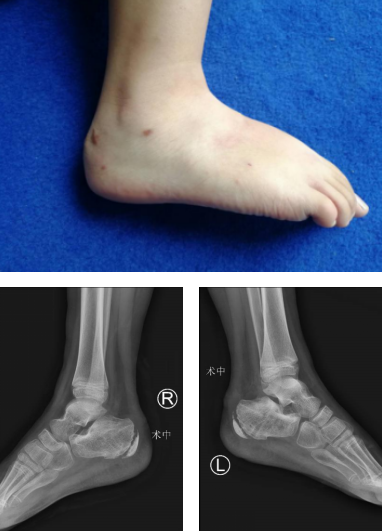

半年后来取内固定

孩子在家康复期间,一直跟主治医生保持联系,出院两个月时跟医生汇报,说已经在家正常行走了。出院6个月后,小吉来取内固定。

取完内固定后,魏医生特地让孩子来回走了几圈,孩子走得轻松自如,“叔叔,我一点也不疼了,每天都下楼玩,但我妈不让我多玩。”“嗯,虽然恢复得不错,玩耍也要适度。”